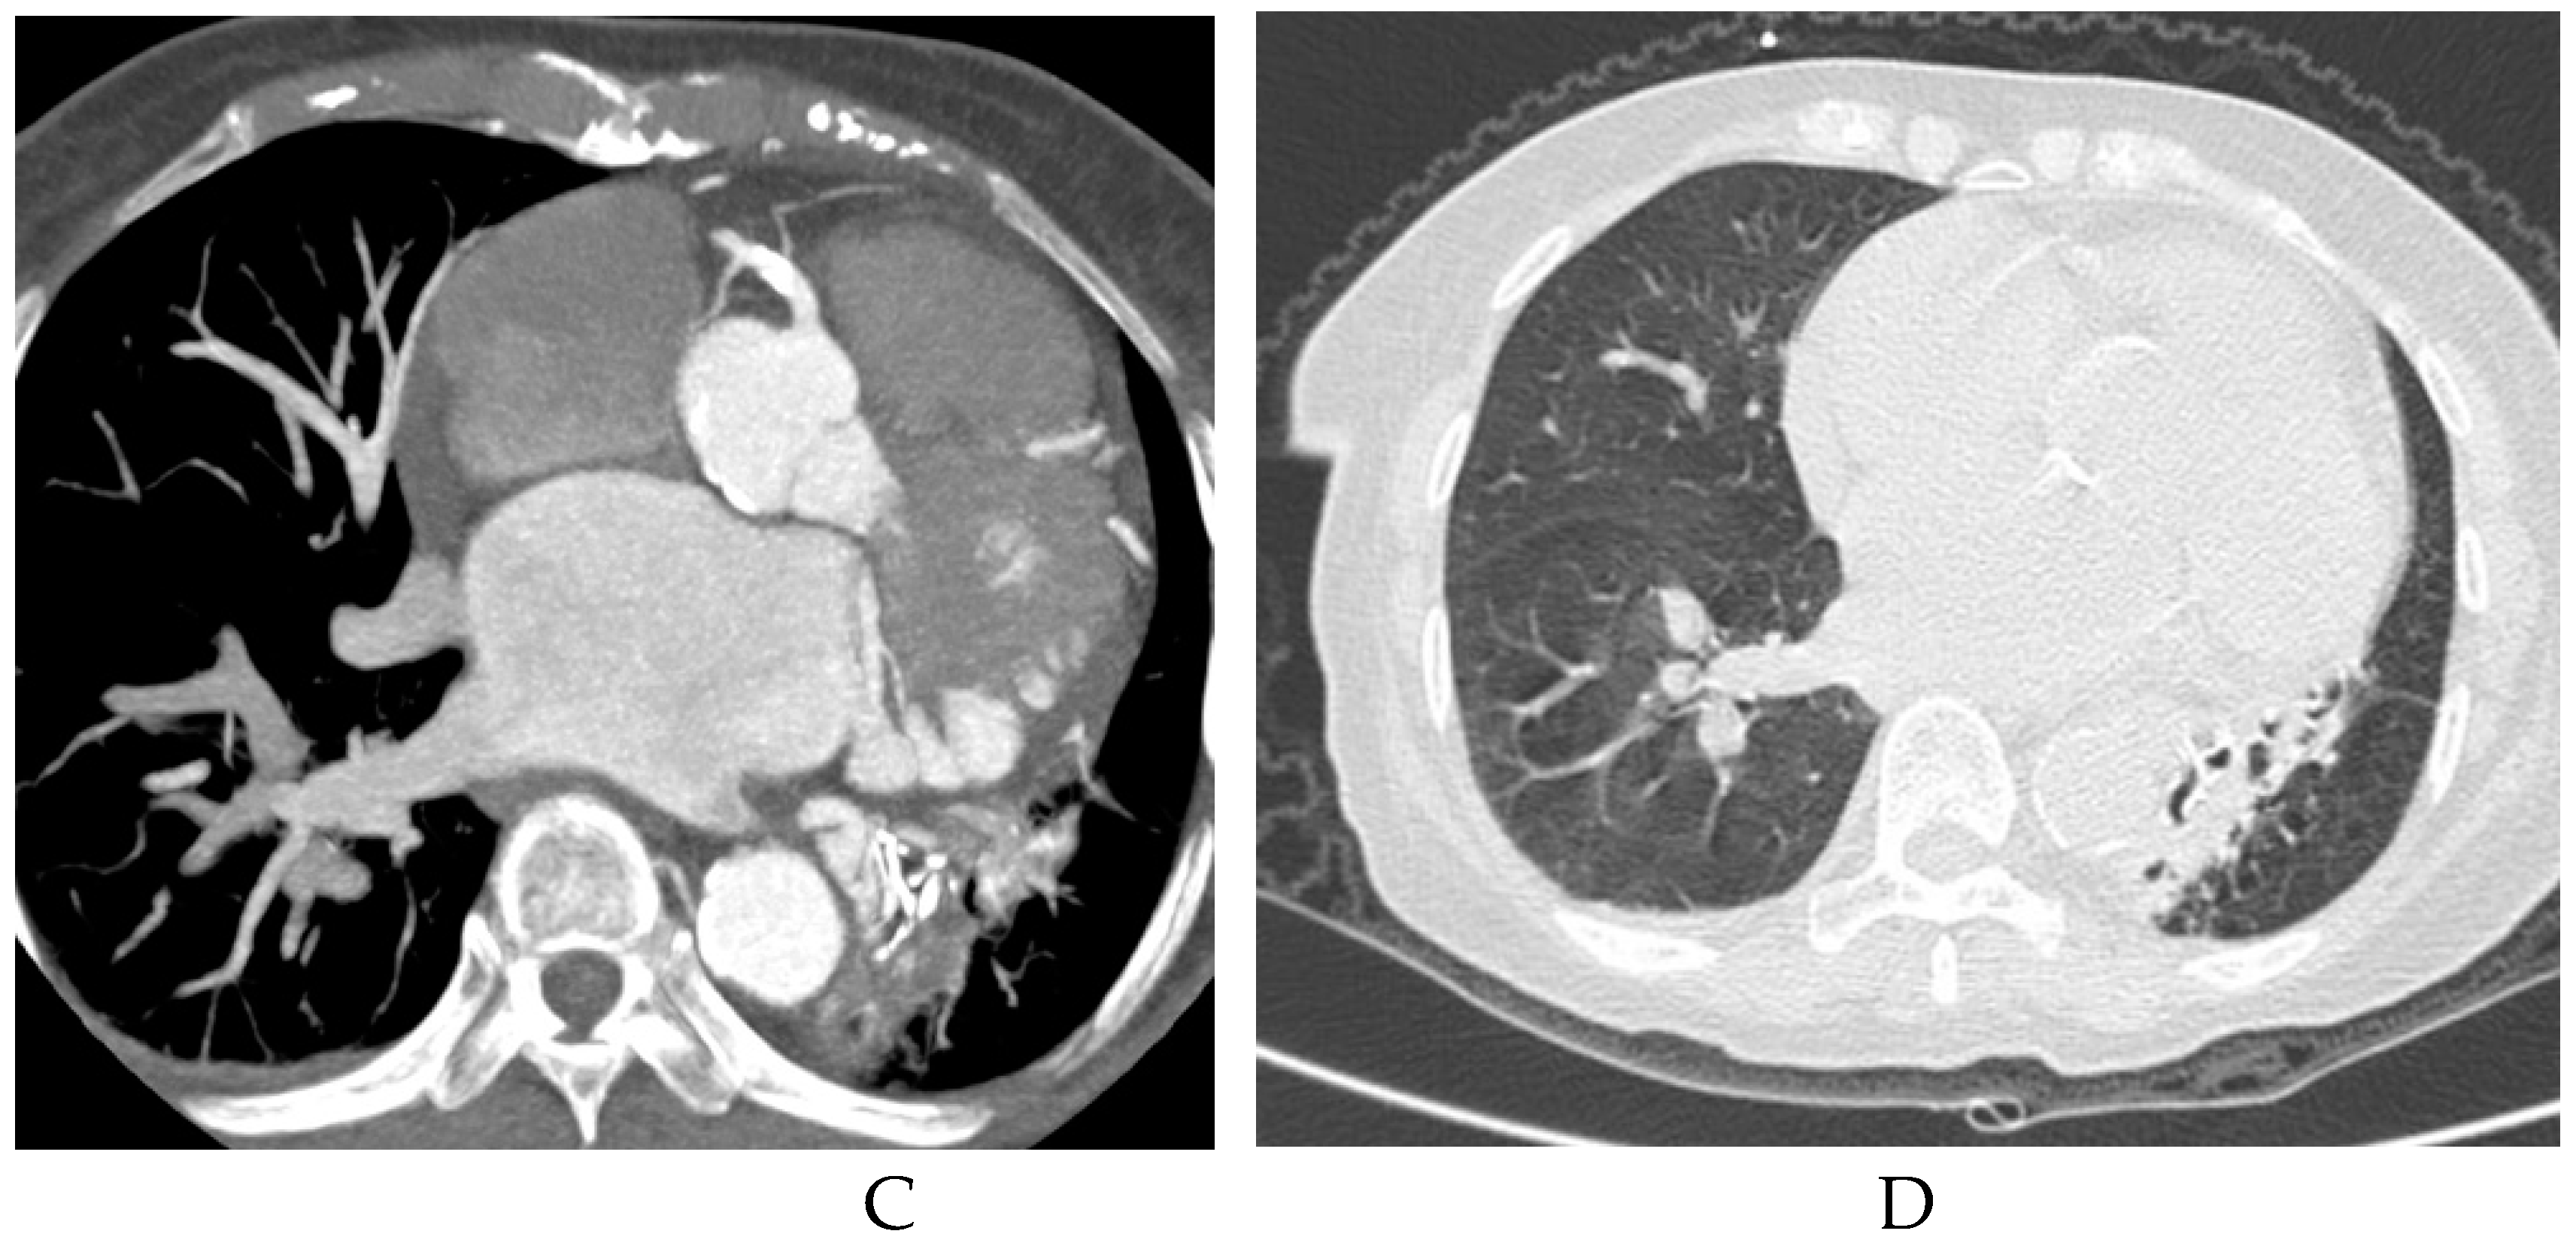

3.2. Imaging appearances of CTPA

- Long, Q.; Zha, Y.; Yang, Z. Evaluation of pulmonary sequestration with multidetector computed tomography angiography in a select cohort of patients: A retrospective study. Clinics. 2016, 71, 392–398. [Google Scholar] [CrossRef]

- Yue, S.W.; Guo, H.; Zhang, Y.G.; Gao, J.B.; Ma, X.X.; Ding, P.X. The clinical value of computer tomographic angiography for the diagnosis and therapeutic planning of patients with pulmonary sequestration. Eur. J. Cardiothorac. Surg. 2013, 43, 946–951. [Google Scholar] [CrossRef] [PubMed]